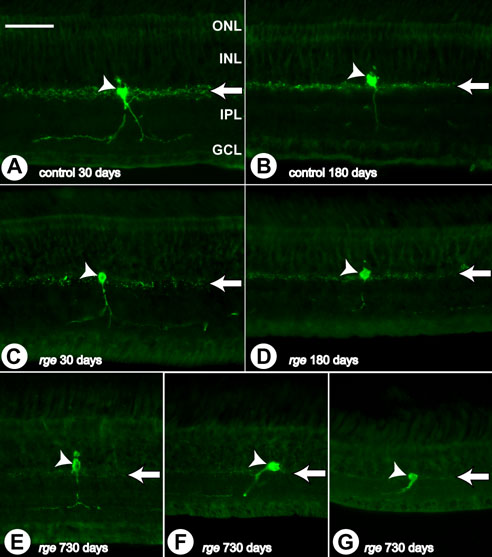

Figure 11. Abnormalities in tyrosine hydroxylase immunohistochemistry

Immunohistochemistry sections using tyrosine hydroxylase (TH) antibody performed on samples from rge/rge and control birds at 30, 180, and 730 days of age. A: Control bird at 30 days of age. B: Control bird at 180 days of age. C: rge/rge bird at 30 days of age. D: rge/rge bird at 180 days of age. E: Central retina of rge/rge bird at 730 days of age. F: Peripheral retina. G: Far peripheral retina. Note that in control retinas, TH positive neurites are found concentrated at the outer border of the IPL, close to the corresponding amacrine cell body. Further neurites from these cells can be observed, at a lesser density, branching bilaterally and extending into the IPL close to the GCL. At later stages of development (180 and 730 days of age) there is an obvious decrease in the density of TH positive neurites in retinal samples from rge/rge birds (compare A,B with C,D; arrows). However, no loss of TH positive somata was observed even at very late stages of the disease (E,F,G; arrowheads). The outer nuclear layer (ONL), inner nuclear layer (INL), inner plexiform layer (IPL), and ganglion cell layer (GCL) are labeled in A The bar represents 50 μm.